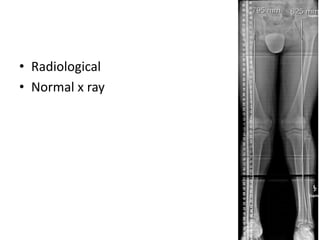

• Radiological

• Normal x ray

• CT Scanogram is a very accurate method of as

long as the measurements are taken

accurately or as long as the scale of the film is

mentioned